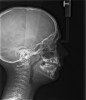

Instinctively, clinicians have concentrated on the mandible when discussing airway dimensions. However, the maxilla appears to be the more important arch in determining upper airway dimensions in OSA patients.45 The distance from A point (most posterior point in the concavity of the anterior maxilla) to Porion vertical (vertical line drawn from the most superior part of the external auditory meatus) was the most contributory cephalometric marker for airway patency. Appropriate positioning of the maxilla opens the velopharyngeal and orophayngeal airways. Additionally, proper maxillary positioning enhances mandibular growth. Thus, the lack of facial muscle activity and ideal tongue tone constrains the premaxilla, producing an abnormal airway dimension and amplifying the threat of SDB.

Tonsils and adenoids should be judged against the relative size of the airway rather than the absolute size of the lymphoid tissue46 (Figure 5 and Figure 6). Adenoids are located at the posterior of the nasal cavity on the roof of the nasopharynx (Figure 7). The normal distance from the adenoids to the soft palate for an acceptable airway should be at least 12 mm. For each millimeter decrease, the odds of the child snoring increase 1.61 times. Mouth breathers typically show a smaller upper airway dimension as well.47 The adenoid and tonsillar obstruction creates the trigger, but the deviate facial and neck muscle recruitment and tongue hypotonia cause the maldevelopment.48

The point of obstruction tends to determine the type of skeletal impact. Nasal obstruction from enlarged turbinates, blocked ostium maxillare, deviated septum, or nasal valve stenosis creates Angle occlusions of Class I, II, and III equally (Figure 8). The maxilla in these cases is positioned posteriorly and the mandible is posterior-inferior. The facial type is most commonly dolicocephalic. Blockage of the airway predominately by the adenoids will create growth patterns that yield mostly Class II occlusions and anterior open bite with both jaws located posterior-inferiorly. Facial type is again dolicocephalic with the typical long-thin “adenoidal” face49 (Figure 9 through Figure 12). If the tonsillar tissue is responsible for the airway obstruction, the tongue will have an abnormal resting posture. Class III occlusions will be more common with the maxilla normal or posterior placed (Figure 13 through 15). The tongue may direct the mandible anteriorly or, because the tongue is not in the roof of the mouth driving A point anterior, the maxilla will become bimaxillary retrusive.50 In some cases, the anterior posture of the tongue will create an open bite. This is incorrectly referred to as a tongue thrust. The impact from a thrust does not alter the tooth position. Long-term, low forces cause tooth movement. The posture of the tongue against or between the anterior teeth due to the excessive tonsillar size creates the open bite (Figure 16 and Figure 17). Facial types in this group are more brachyfacial. Lastly, if the airway is blocked through a combination of factors, the Angle classification will be either Class II or III. The maxilla will be in a normal location and the mandible will be the affected arch (Figure 18). These craniofacial changes are not restricted to OSA; all SDB will create unique alterations depending on the patient compensation. Children with UARS have been reported to display high, narrow palates, dolicofacial form, and a Class II malocclusion, indicative of largely adenoidal blockage.51

Figure 11

(11.) Adenoidal tissue blocking the velopharyngeal airway.